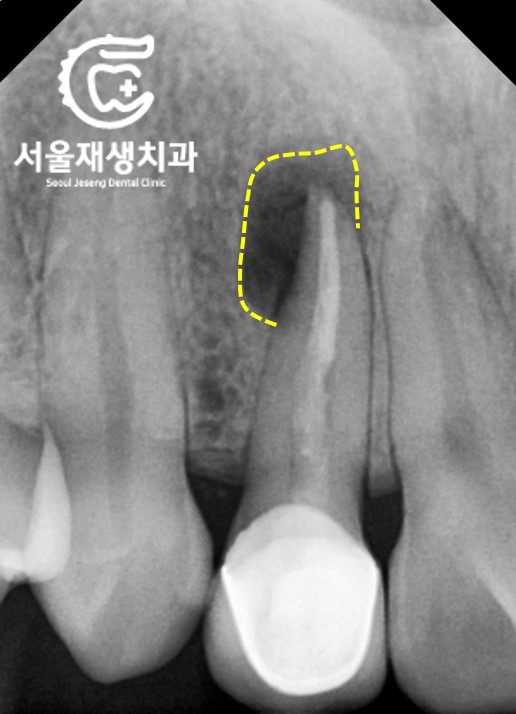

파노라마 엑스레이

![[재신경치료] 소중한 내 앞니...재신경치료로 다시 한 번 살려 쓸 수 있습니다. (서울재생치과, 현미경신경치료) 관련 이미지 3](https://pub-9f2bb3498faf4d1d8714b41df24753e3.r2.dev/content/clinics/archive/nqmm0udu86/naver_blog/honeybeevuvu/assets/by_hash/943b25df7e89de742f550a3af247f75bab9cabe2a4abcd1c63d3b2303e150fa9.jpg)

치과 검진을 위해 가장 기본적으로

촬영하는 사진입니다.

파노라마 엑스레이라고 하는데요,

원인이 되는 치아의 정확한 위치와

대략적인 컨디션을 파악할 수 있는

가성비 최고의 검사입니다.

노란상자로 표시된 부분을 보겠습니다.

앞니의 뿌리 끝에

검은 구멍이 보이네요.

염증 때문에 뼈가 흡수된 것 같습니다.

좀 더 자세히 살펴보겠습니다.